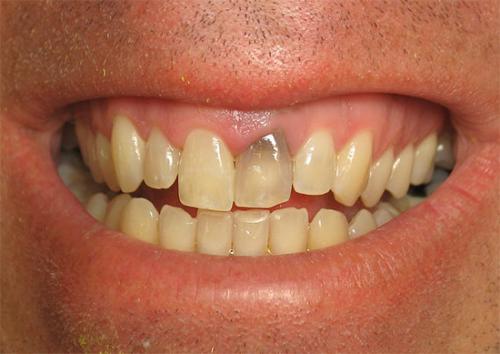

Черный прыщик во рту на щеке. Локализация и цвет сыпи

Доктор на осмотре обращает внимание на месторасположение язв внутри рта и их оттенок. Высыпания появляются с внутренней стороны губ, на слизистой оболочке щек, языке или горле. Как видно на фото, они могут быть красного, розового, белого или коричневого цвета. Красные прыщики во рту (на языке, щеке, небе) чаще всего являются признаком инфекционного заболевания у взрослого или ребенка. Человека сопровождают сильные боли при употреблении пищи или разговоре. Белые (бывают слегка желтоватыми) точки – проявление стоматита или вирусной болезни. Коричневые или черные шишки говорят о серьезной патологии, которая перешла в запущенную стадию и вызвала отмирание тканей.

Задать вопрос экспертуПрыщ на губе внутри рта может подсказать о травме слизистой оболочки острыми предметами, ожоге, несоблюдении гигиены или инфекции. Наиболее часто такие высыпания имеют белый или желтый цвет. При переходе в тяжелую стадию поражают большую площадь и становятся красными. Приносят боль как при пальпации, так и при приеме пищи.

Поражение слизистой оболочки на щеках вызвано болезнями стоматологического характера и травмами, а также нарушениями в работе внутренних органов. Зачастую язвочки образовываются у пациентов с гастритом или другими патологиями желудочно-кишечного тракта. Оттенок может быть белым или красным, форма – круглая, размер различный, иногда доходит до образования больших бляшек.